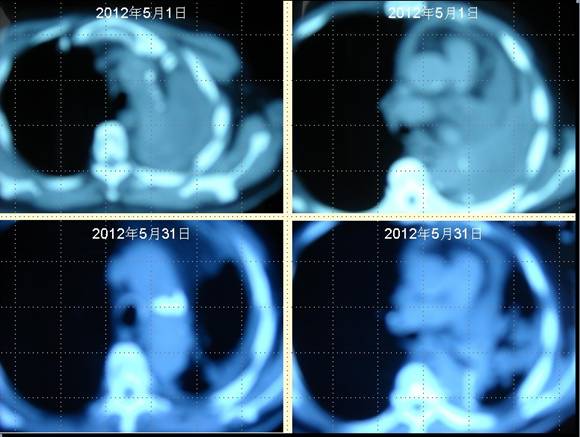

[提要] 患者王某某,男,74歲,于2009年12月在濱州醫學院附屬醫院行左肺下葉占位切除術,術后病理提示為“中分化鱗狀細胞癌”侵犯支氣管壁全層,累及支氣管周圍肺組織。術后化療4個周期,局部放療30次(具體方案及劑量均不詳),2011年病灶局部復發,口服“特羅凱”“康力欣”等無效,于2012年5月1日復查肺CT示:心包積液,左側包裹性胸腔積液,后縱膈結節影,右側少量積液。經采用“中醫調胃、強腎、止血、化巖法”治療1個月,胸腔積液完全消失,心包積液明顯減少,未出現新癌灶。

患者王某某,男,74歲,于200912月在濱州醫學院附屬醫院行左肺下葉占位切除術,術后病理提示為“中分化鱗狀細胞癌”侵犯支氣管壁全層,累及支氣管周圍肺組織。術后化療4個周期,局部放療30次(具體方案及劑量均不詳),2011年病灶局部復發,口服“特羅凱”“康力欣”等無效,于201251日復查肺CT示:心包積液,左側包裹性胸腔積液,后縱膈結節影,右側少量積液。經采用“中醫調胃、強腎、止血、化巖法”治療1個月,胸腔積液完全消失,心包積液明顯減少,未出現新癌灶。

肺癌王XX采用 “董氏治癌法”治療前后CT對照變化